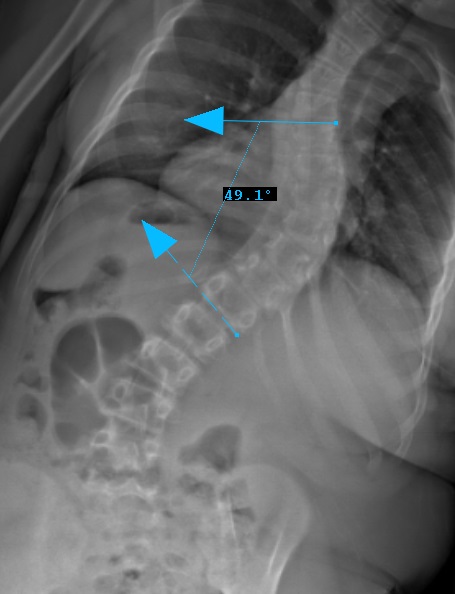

Preop LEFT Bend

Preop RIGHT Bend